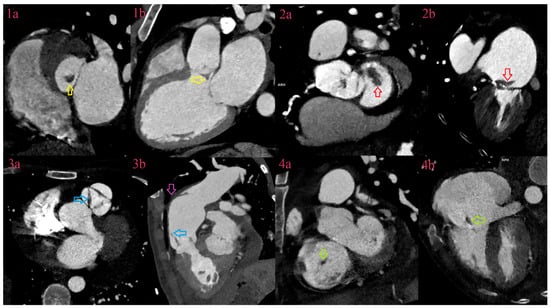

3.6. Abscesses

3.7. Pseudoaneurysms

3.8. Fistulas

3.9. Leaks